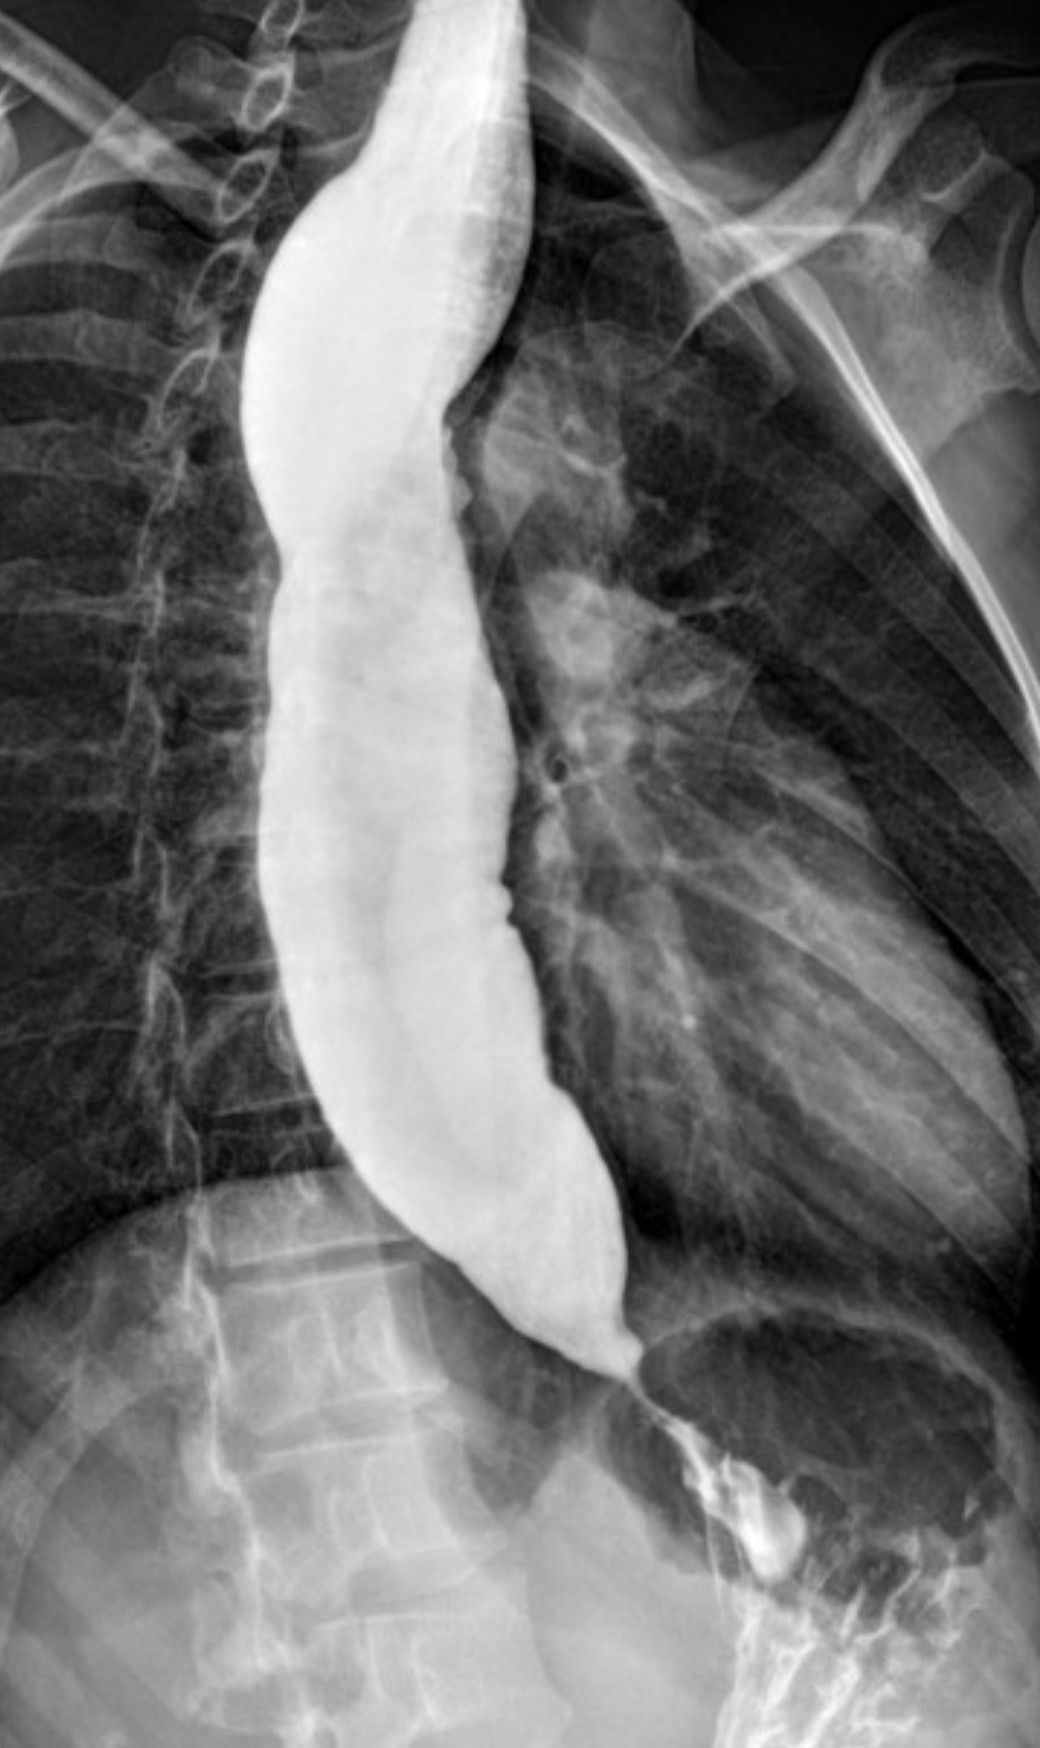

Achalasia is a disease in which there is loss of peristalsis in the distal esophagus and lower esophageal sphincter also fails to relax. The symptoms include chest discomfort, dysphagia for both solids and liquids. The classic radiographic finding is bird beak appearance. Surgical treatment is Hellers myotomy, balloon dilatation and for medical treatment calcium channel blockers can be used.